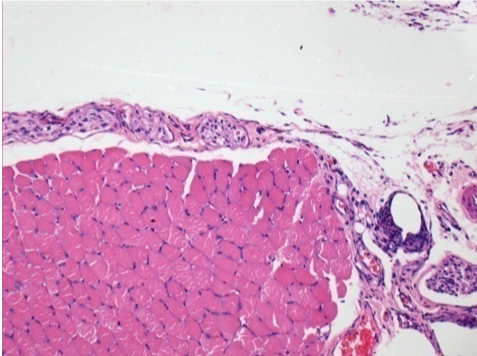

10 Inyección subcutánea

0,5 ml (5 x 0,1 ml) Endopeel SC Inyección en el área pretibial subcutánea derecha.

L:200x-Control-SC

R-D10-SC-200X

R-D30-SC-200X

R-D90-SC-200X

R-D210-SC-200X

R-D210-SC-400X